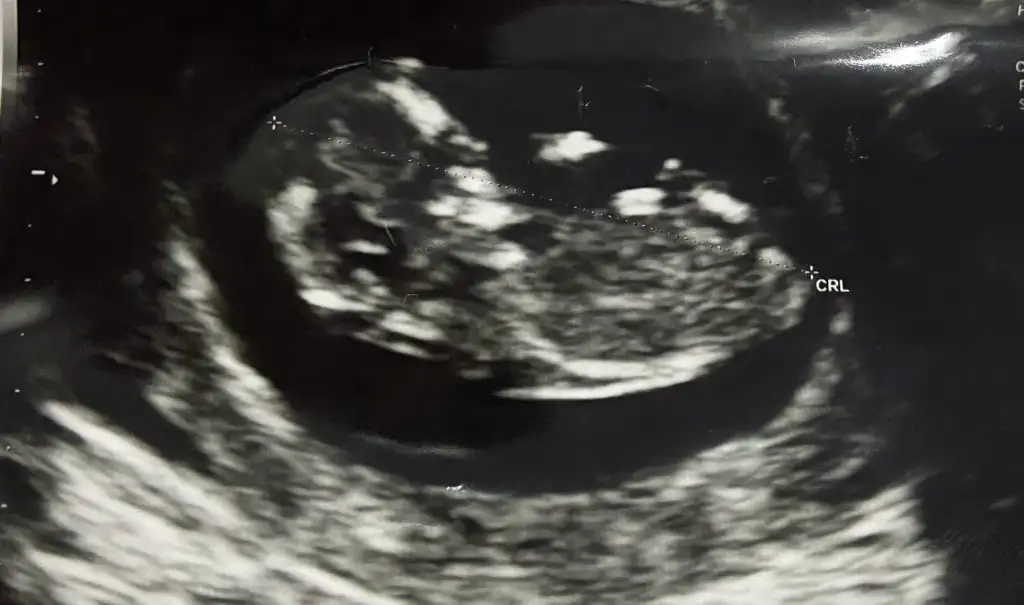

Selam kizlar bir iki gundur yoktum burda bazi rahatsizliklar gecirdim hastaneyle ugrasip duruyorum . Tansiyonum 16 lara kadar cikti asiri bir carpinti basladi allahtan buyuk bir sorun cikmadi. Normaldedr kalp hastasiyim zaten vucumuz normalden fazla fkan uretmeye baslayip kalp fazladan calisinca boyle seyler olabiliyormus. Eger sizlerdede olursa paniklemeyin hastaneye gitmisken birdr bebisimi goreyim dedim inanilmaz hareketli asla yerinde durmuyor doktor cok guldu hatta bu neler yapiyor boyle diye cinsiyet icinde 12. Hafta soyleriz dedi, inanilmaz kiz istiyorum ama erkek hissediyorum bakalim neler olacak